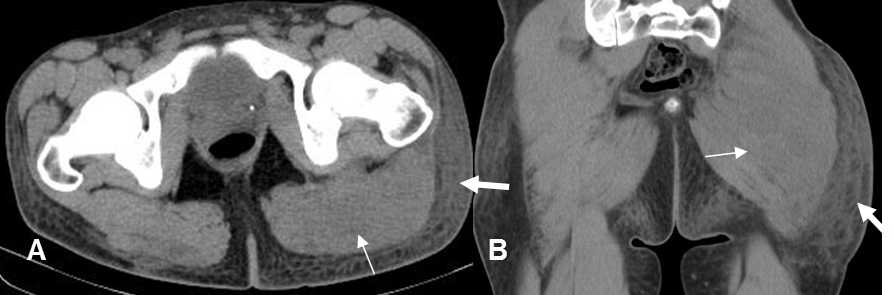

Fig 16. Flemón de tejidos blandos.

A: TAC axial y B: TAC coronal. Prominencia de los músculos en la región glútea izquierda, sin identificar colecciones, por flemón. (Flechas delgadas). Igualmente hay trabeculación y aumento en la densidad de la grasa, por celulitis. (Flechas gruesas).